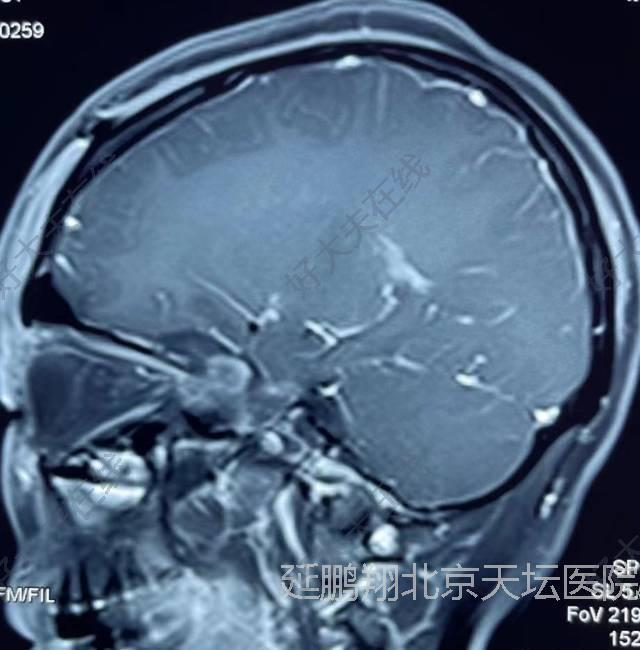

治疗中

手术在全麻下进行,釆用左额颞入路,先切断肿瘤基底,阻断血供。肿瘤质地软,与脑组织粘连不紧,易分离,两者相隔有蛛网膜(图2),肿瘤切除后左侧嗅神经,视神经,颈内动脉,动眼神经均保护完好(图3)。